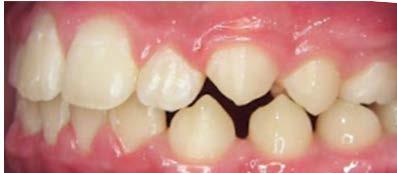

58 | CASO CLÍNICO

Tratamiento de mordida profunda, con arco utilitario, en paciente en crecimiento